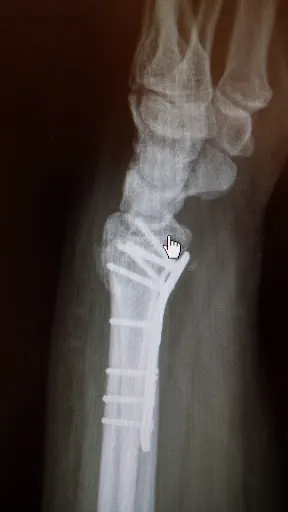

Lek. Kamil Wilga to specjalista ortopedii prowadzący praktykę w Ciechanowie przy ul. Powstańców Wielkopolskich 2. W dogodnej lokalizacji w centrum miasta oferuje konsultacje pacjentom zmagającym się z problemami układu ruchu. Gabinet cieszy się doskonałą opinią na Google – średnia ocena 5.0/5 na podstawie trzech recenzji, co świadczy o wysokim poziomie zadowolenia klientów. Pacjenci chwalą doktora za profesjonalne podejście i indywidualne traktowanie. Jeden z nich podkreśla pomoc w dolegliwościach związanych z urazem kolanowym, doceniając fachową opiekę. Inni zwracają uwagę na empatię i spokojne wyjaśnienia – „najbardziej empatyczny lekarz, na jakiego trafiłam” – brzmi jedna z opinii. Kolejny pacjent jest pod wrażeniem holistycznego spojrzenia na problemy zdrowotne, co buduje zaufanie i poczucie bezpieczeństwa. W Ciechanowie, gdzie dostęp do specjalistów ortopedii bywa cenny, lek. Kamil Wilga wyróżnia się spokojem i precyzją w komunikacji. To wybór wart rozważenia dla osób szukających rzetelnej pomocy medycznej w przyjaznej atmosferze. (198 słów)